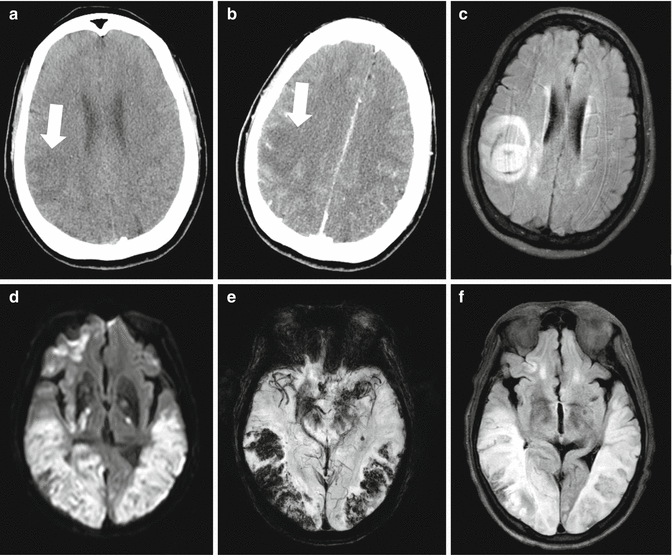

Fig. 3.1

Representative cases of stroke mimics. The first case (a–c) is a 65-year-old woman who complained of sudden onset left-side weakness and hypesthesia. Initial pre- and post-gadolinium (a, b) brain CT showed low-attenuated lesion involving right postcentral gyrus without enhancement (white arrow). Since initial symptom onset was within 3 h, she was treated by intravenous thrombolysis, but weakness progressed thereafter. Subsequent brain MR imaging (MRI) with T2-based fluid-attenuated inversion recovery protocol showed edematous mass lesion with heterogeneous signal intensity and fluid-fluid level. Further evaluation with serial brain MRI and biopsy revealed brain abscess as a final diagnosis. The second case (d–f) is a 62-year-old woman who was found to be in a comatose state at home. Initial neurological examination revealed semicomatose mental status and left-side dominant weakness with extensor Babinski reflex. Brain MR imaging showed diffuse high-signal intensity from diffusion-weighted image and low-signal intensity from susceptibility-weighted image mainly involving both parietal and occipital cortices. Admission serum glucose level and osmolality at admission were significantly elevated, and she was diagnosed as hyperosmolar hyperglycemic coma